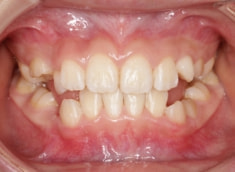

治療後(1年5ヶ月後)

治療開始から11ヶ月